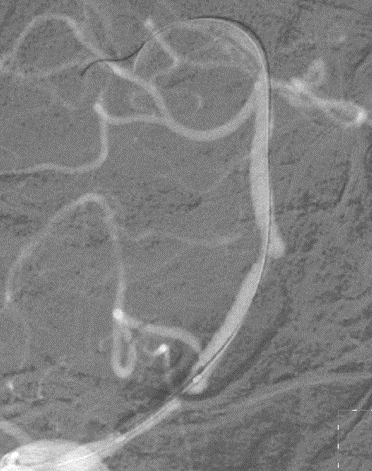

右椎动脉造影:

导丝怎么扩【载药时代 球扩天下】NOVA DES®颅内药物洗脱支架在椎动脉颅内段重度狭窄的应用二例_https://www.jmylbn.com_新闻资讯_第24张

导丝怎么扩【载药时代 球扩天下】NOVA DES®颅内药物洗脱支架在椎动脉颅内段重度狭窄的应用二例_https://www.jmylbn.com_新闻资讯_第25张

导丝怎么扩【载药时代 球扩天下】NOVA DES®颅内药物洗脱支架在椎动脉颅内段重度狭窄的应用二例_https://www.jmylbn.com_新闻资讯_第26张

右椎动脉动脉正侧位:

诊断

主要诊断:

1.右侧椎动脉V4段重度狭窄(90%);

2.高血压病2级 高危;

3.小脑梗死。